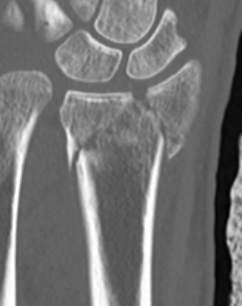

CT for further evaluation of articular congruency

1.  Distal radial Step > 2mm

- leads to RC OA radiographically

Distal Radius Fracture Articular Step Coronal CTDistal Radius Fracture Articular Step Sagittal CT

2.  Articular incongruency sigmoid notch / DRUJ > 2 mm

Distal Radius Fracture DRUJ incongruent